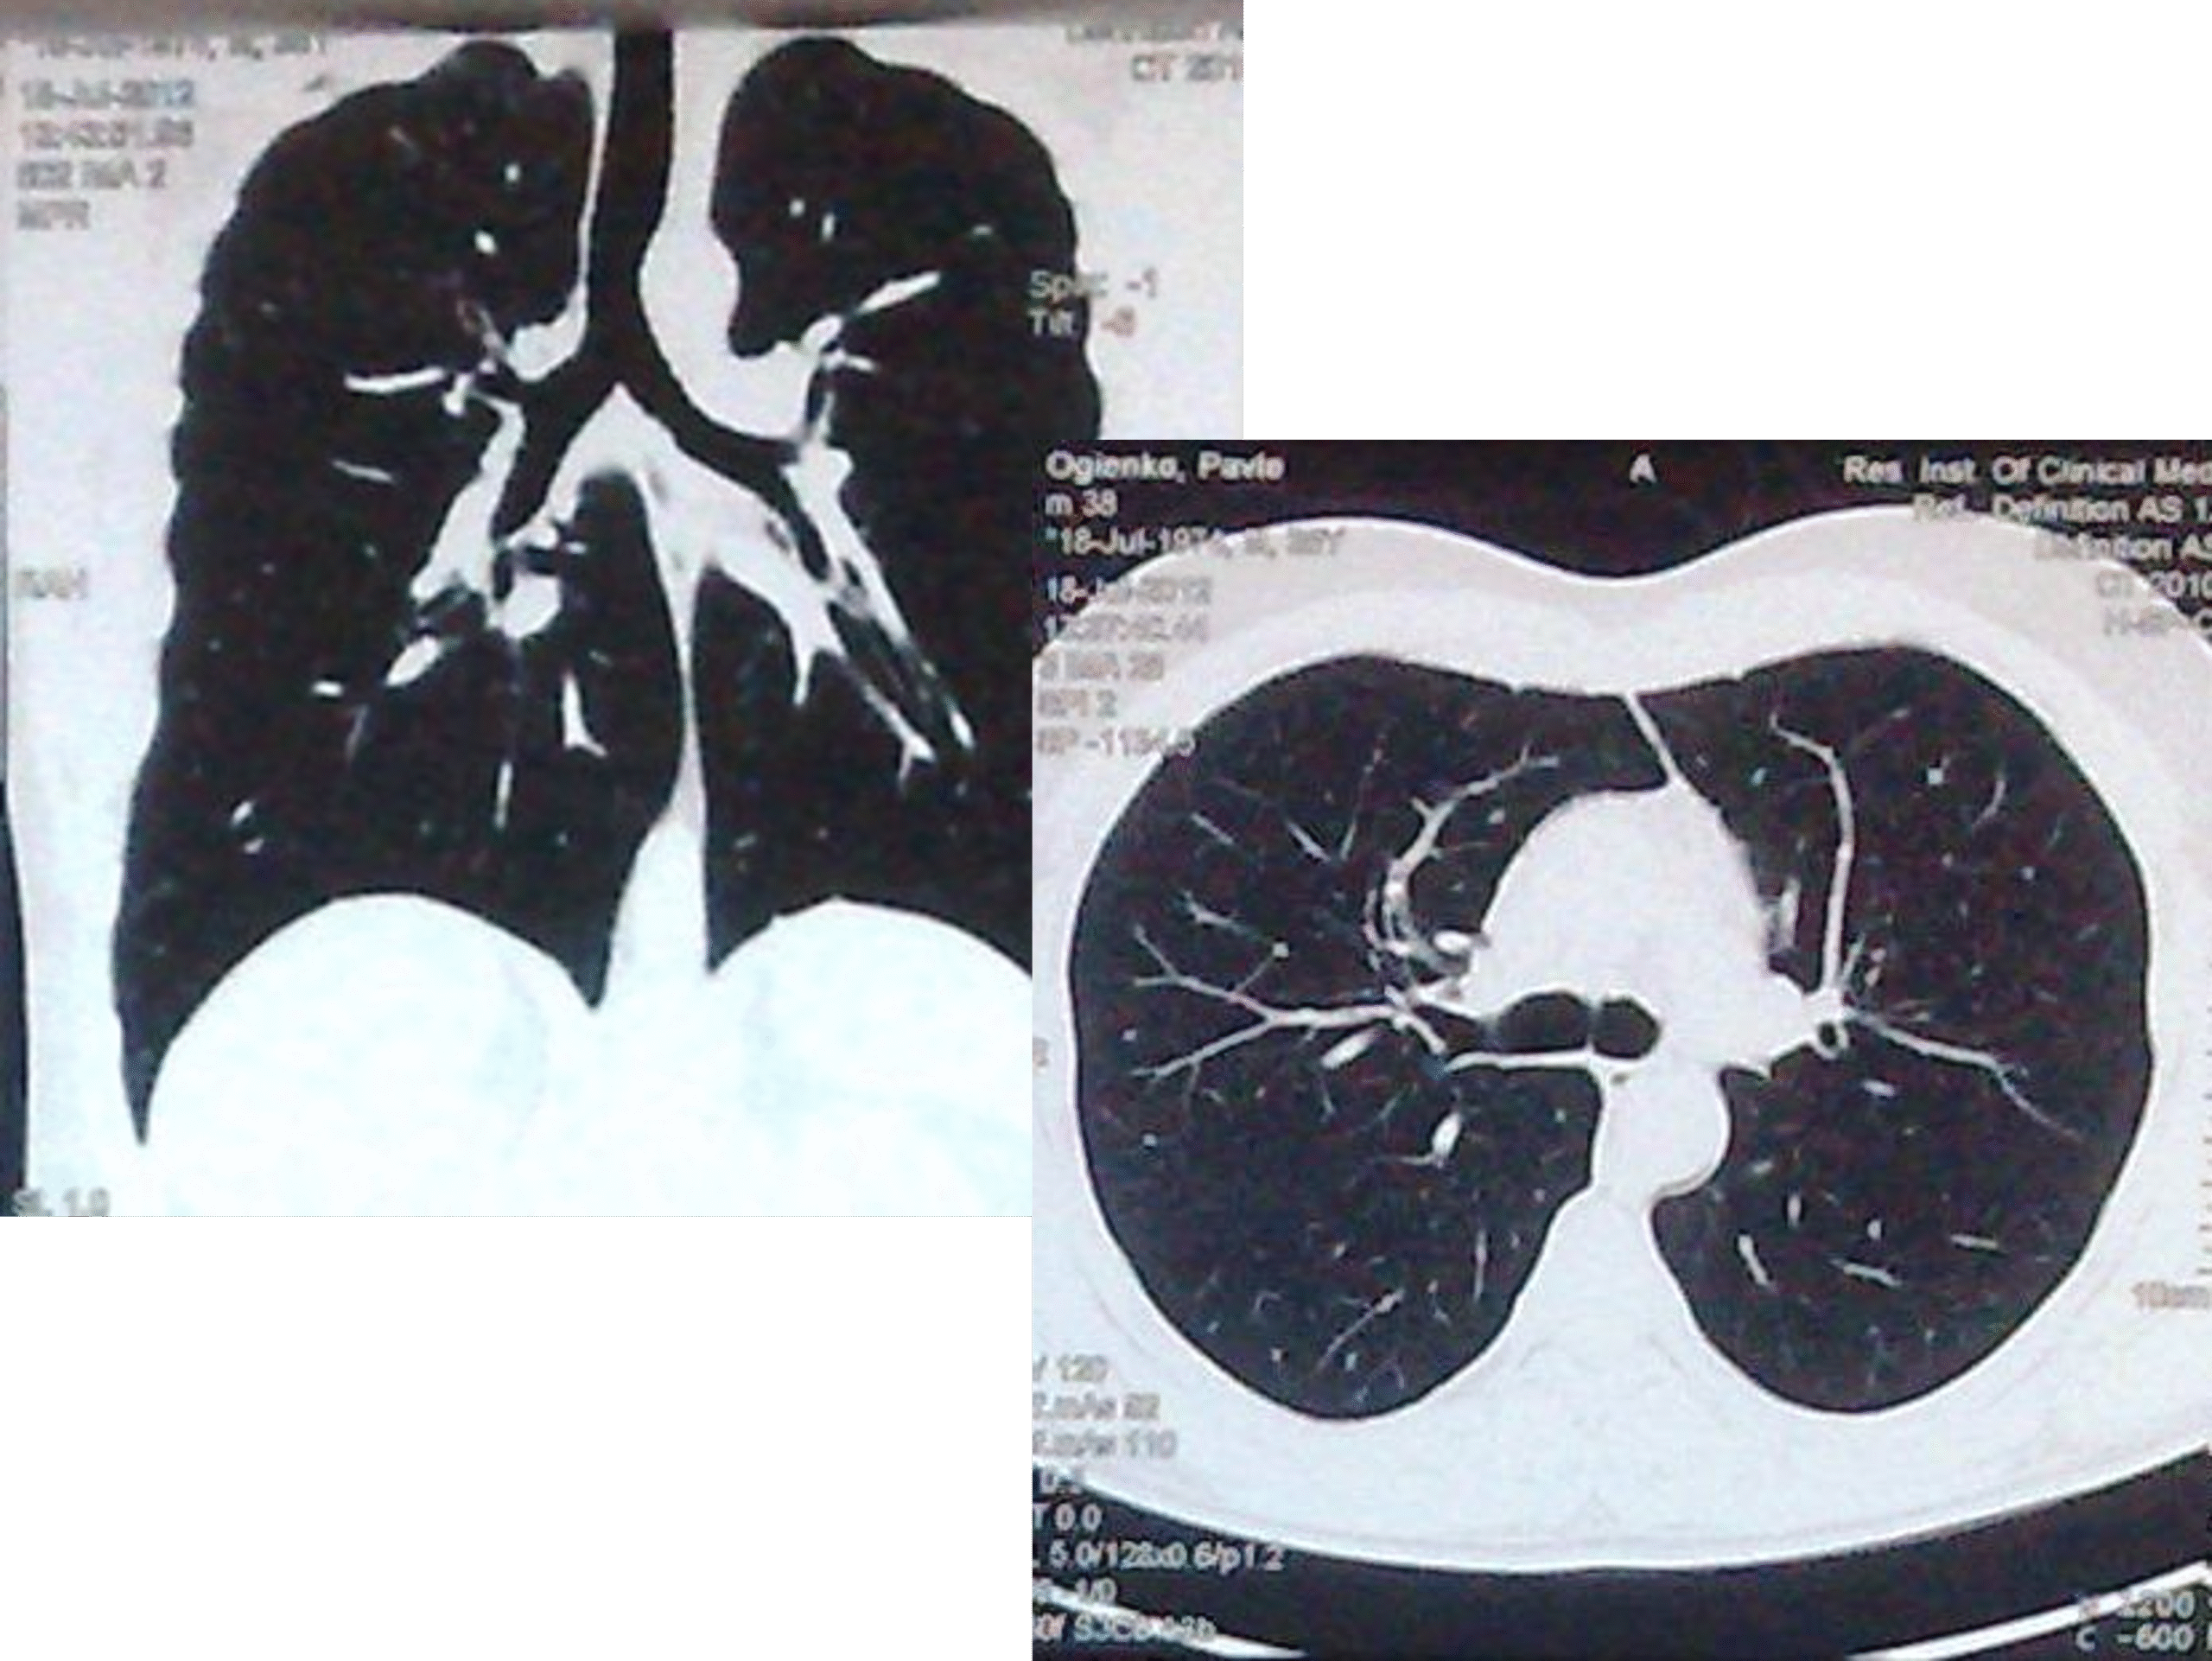

- გულმკერდის კტ რეზექციიდან 4 თვეში